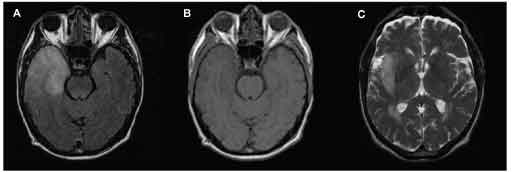

The patient was given a loading dose of intravenous phenytoin (1200 mg) and intravenous acyclovir at a dosage of 10 mg/kg every 8 hours for a total dose of 30 mg/kg/d. On hospital day 2, he withdrew from pain but was unresponsive to voice. A gadolinium-enhanced MRI scan of the brain revealed a hyperintense lesion of the right anterior temporal lobe on T2 fluid-attenuated inversion recovery (FLAIR), which was hypointense on T1 and extended into the adjacent inferior frontal lobe (Figure 2).

Figure 2 – A gadolinium-enhanced MRI scan of the head shows a hyperintense lesion of the right anterior temporal lobe on a T2 fluid-attenuated inversion recovery image (A), which was hypointense on T1 (B), and extended into the adjacent inferior frontal lobe on T2 (C).